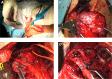

Malignant Shamblin III Carotid Body Tumors Resected with Use of the Retrocarotid Dissection Technique in 2 Patients

Carotid body tumors are rare neoplasms with malignant potential in 6% to 12.5% of cases, and surgical resection is the only cure. We present the cases of 2 female patients who had expanding, painless, right-sided neck masses; computed tomographic angiograms revealed Shamblin III tumors at the carotid bifurcation. Each patient underwent tumor resection with use of the retrocarotid dissection technique. The tumor specimens were histologically consistent with malignancy, and free margins were achieved. The patients remained free of symptoms, local recurrence, and metastasis 44 and 19 months after their respective procedures. These are the first malignant Shamblin III carotid body tumors that we have resected by means of retrocarotid dissection. In addition to our patients' cases, we discuss carotid body tumors and compare the retrocarotid and standard caudocranial resection techniques.